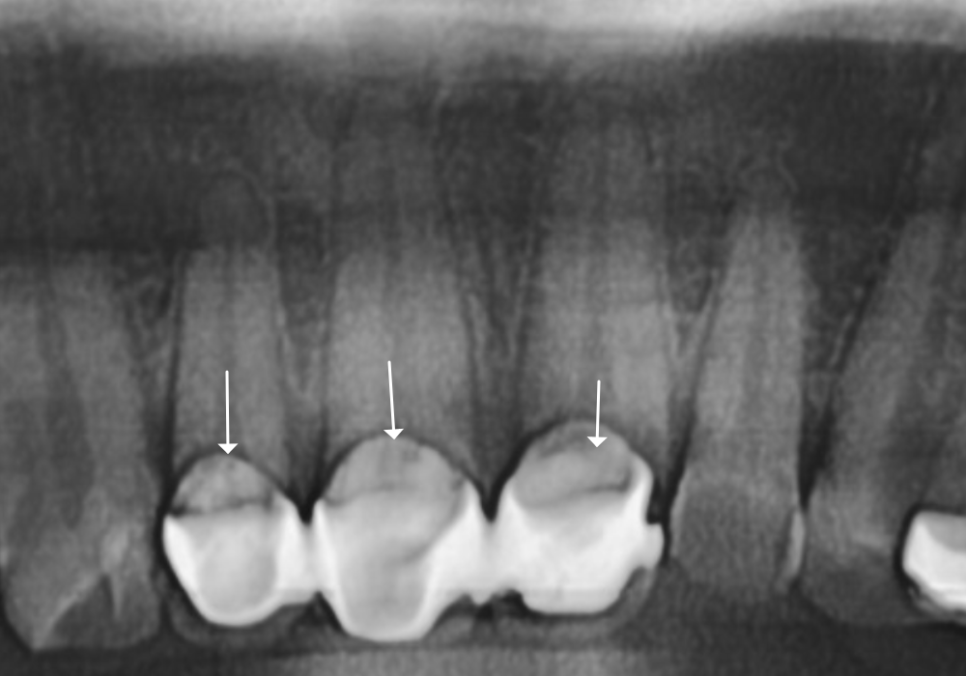

금이나 도자기로 씌운 치아는

엑스레이를 찍어도 이렇게 하얗게 나와요.

즉, 내부가 투과되지 않습니다.

그래서 안쪽에 충치가 얼마나 진행되었는지

정확히 파악하기가 힘들 수 밖에 없어요.

보철물 속은 엑스레이로도 잘 보이지 않아서

겉으로 드러나는 신호를 잘 살펴야 해요.

방사선 상, 보철 경계 부위가

까맣게 나타나는 것을 보아

아무래도 2차 충치의 가능성이 높아

브릿지를 제거해보기로 했습니다.